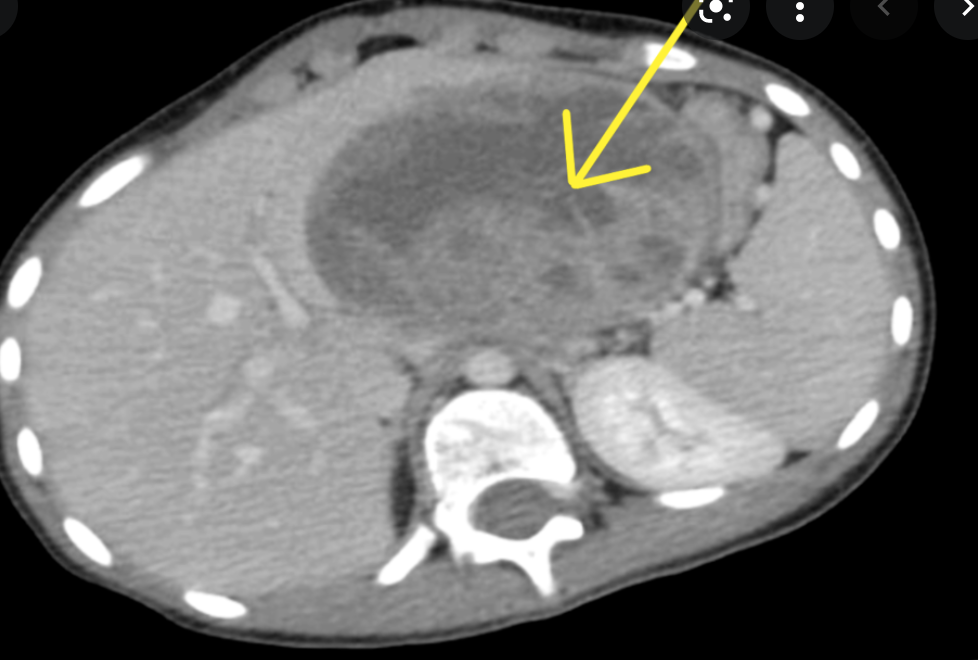

Single phase CT scan (multiphase scans not performed due to age of patient) demonstrates a diffusely enlarged pancreas with a “halo” like rim of hypoattenuating tissue which is smoothly marginated. Minimal peripancreatic fat stranding.

Associated splenic vein thrombosis, splenomegaly and cavernous transformation of the portal vein.